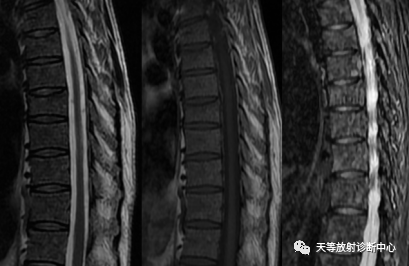

▲上图:骨髓瘤容易漏诊,这样的颈椎信号,信号混杂,很难发现骨质破坏,常常是考虑红黄骨髓分布不均导致的信号混杂,或者椎体骨质疏松信号改变。然而,在随访中证实是多发性骨髓瘤。

▲同上一个病例,这样的信号,也是容易漏诊骨髓瘤。后面随访中确诊骨髓瘤。

▲同上一个病例,通过后面随访,病变范围扩大,明显溶骨性骨质破坏。